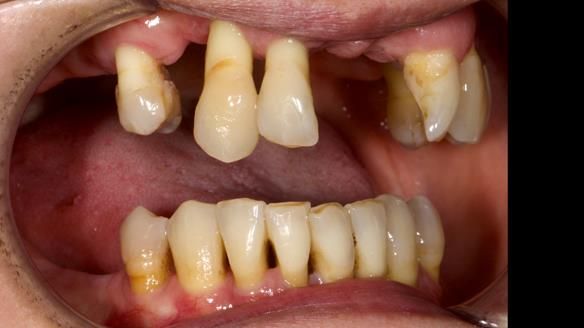

We provided her with an immediate upper denture (Mk 1), followed by a definitive metal-based upper denture (Mk 2). A lower removable partial denture was discussed, to be made only if needed once the upper treatment was complete. However, at review, this wasn’t necessary — Adnana had excellent neuromuscular control and function, even with a shortened dental arch (SDA).

Rowan, Sam Hesketh and Chris Hesketh provided the stunning technical work. I am very lucky to have them.

- Immediate denture (Mk 1) fitted the same day the teeth came out

- Definitive denture (Mk 2), metal-based and custom-designed for her face

- A restored smile, restored lip support, and a patient who owned the journey